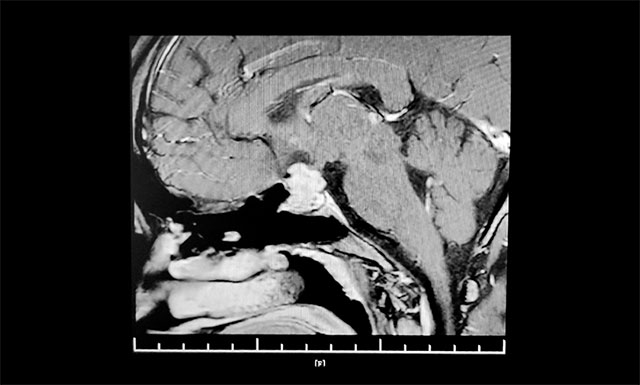

▲ 術(shù)前影像:垂體大腺瘤,向鞍上生長(zhǎng)

鞍區(qū)MRI平掃+增強(qiáng)顯示:蝶竇顯著擴(kuò)大,鞍區(qū)見(jiàn)腫塊影,鞍膈初見(jiàn)“腰征”,灶區(qū)矢橫高徑約1.8*2.0*2.0mm。病變向鞍上生長(zhǎng),占據(jù)鞍上池,推移視交叉。

上海藍(lán)十字腦科醫(yī)院神經(jīng)外科6B病區(qū)主任潘仁龍指出,垂體腫瘤向鞍上生長(zhǎng),占據(jù)鞍上池,壓迫到視神經(jīng)傳導(dǎo)物,使患者視物出現(xiàn)異常。一般1-3cm的大腺瘤或大于3cm的巨大腺瘤,都會(huì)引起不同程度的視力問(wèn)題。